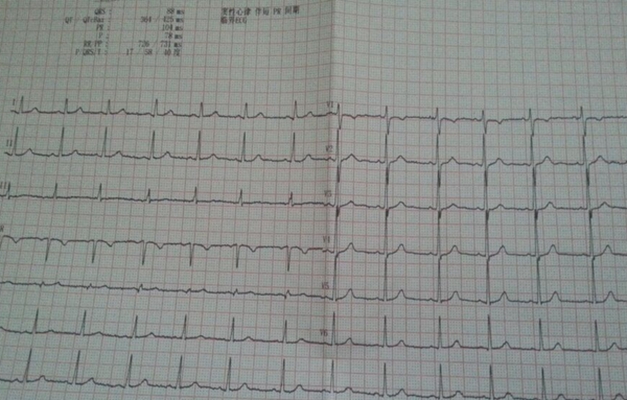

預激綜合徵心電圖 (82)

預激綜合徵心電圖 (83)

預激綜合徵心電圖 (84)

預激綜合徵心電圖 (85)

預激綜合徵心電圖 (86)

預激綜合徵心電圖 (87)

預激綜合徵心電圖 (88)

預激綜合徵心電圖 (89)